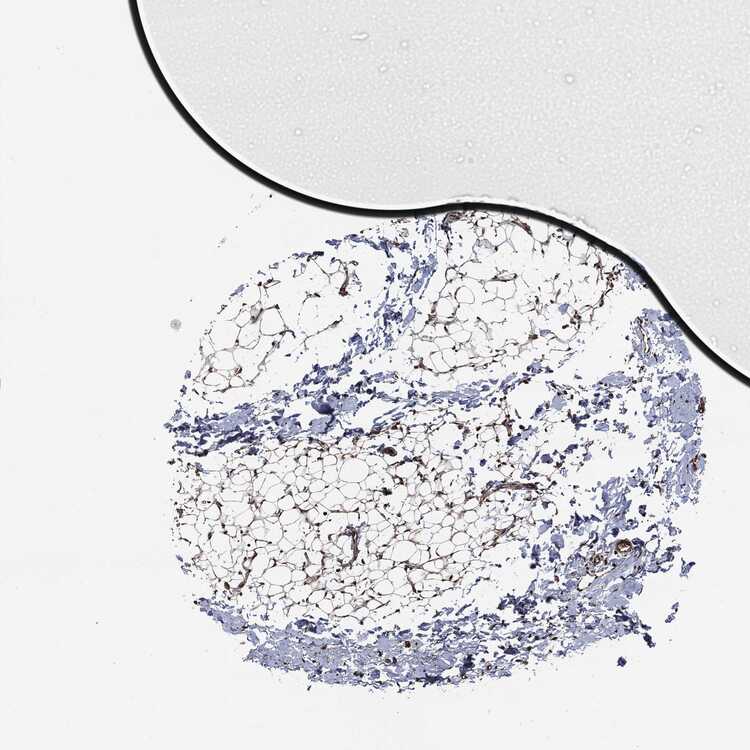

BREAST - Antibody stainingi

Antibody staining in the annotated cell types in the current human tissue is reported as not detected, low, medium, or high, based on conventional immunohistochemistry profiling in selected tissues. This score is based on the combination of the staining intensity and fraction of stained cells.

Each image is clickable and will lead to virtual microscopy that enables deeper exploration of all samples and also displays staining intensity scores, fraction scores and subcellular localization as well as patient and tissue information for each sample.

Antibody HPA069985Antibody CAB005883Antibody CAB078687Antibody CAB080398

Adipocytes HighNot detectedNot detectedHigh

Glandular cells HighHighNot detectedMedium

Myoepithelial cells MediumHighNot detectedMedium